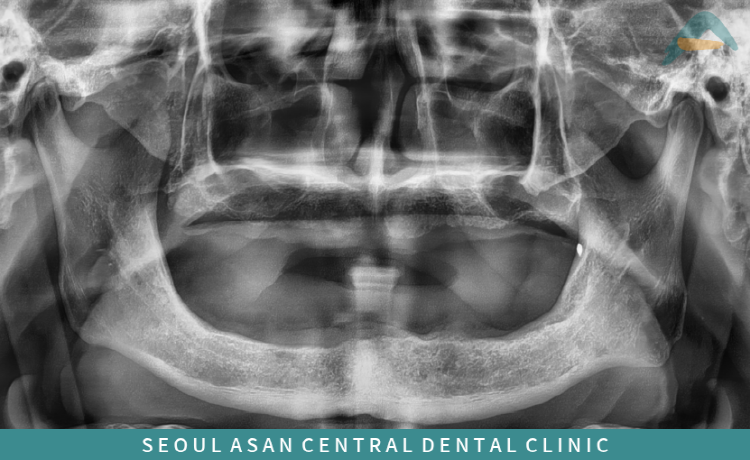

성남치과 임플란트 식립 과정

성남치과 서울아산센트럴에서는

임플란트 틀니(오버덴처) 진행 전

파노라마 및 3D CT 촬영을 통해

잇몸뼈 상태와 구강 구조를

정밀하게 확인하고 있습니다.